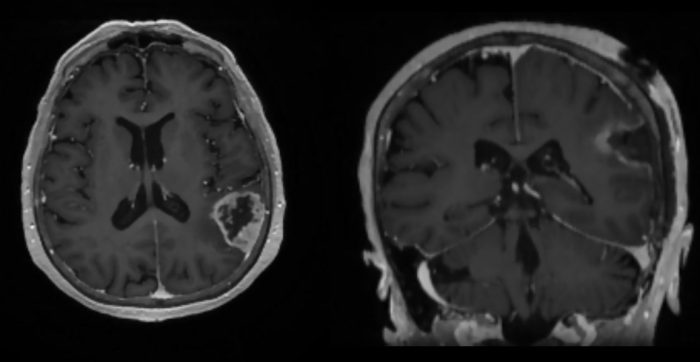

Как рассказали в пресс-службе Новосибирского НИИТО им. Я.Л. Цивьяна, в декабре 2025 года врач-фтизиатр с 30-летним стажем (на пенсии) Татьяна отметила 81-й день рождения. А незадолго до этого впервые почувствовала резкое ухудшение здоровья: упало зрение, появилась слабость, конечности онемели. В какой-то момент словно случился инсульт. Женщина обратилась к коллегам и оказалась в сосудистом центре. Сначала состояние стабилизировалось, но вскоре пенсионерка вдруг стала заикаться. МСКТ и МРТ головного мозга выявили опухоль в левой теменной доле, которая и вызвала проблемы.

Как подчеркивают в НИИТО, хирургическое лечение возрастных пациентов требует учитывать множество факторов, связанных с сопутствующими заболеваниями, физиологическими изменениями всех систем организма, нарушением метаболизма и повышенным риском осложнений. Из-за этого нужна слаженная командная работа врачей разных специальностей, мультидисциплинарный подход. В феврале 2026 года Татьяну планово госпитализировали. К счастью, опухоль 3×4×5 см успешно удалили с использованием нейронавигации для минимального травмирования тканей. После операции пациентку направили на дальнейшее гистологическое обследование.